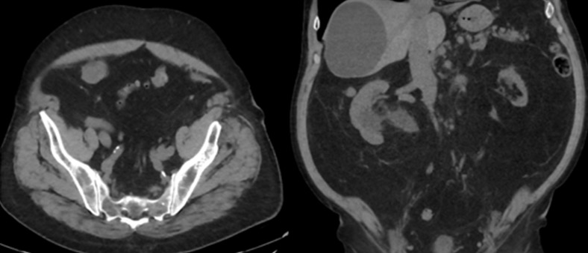

74-year-old male with a past medical history of nephrolithiasis, sleep apnea, thoracic aortic aneurysm, activated protein C resistance, Factor V deficiency, Gout, Hypertension and benign prostatic hyperplasia (BPH) presented for further evaluation regarding nephrolithiasis. The patient recently underwent extracorporeal shock wave lithotripsy (EWSL), and a post operative abdominal x-ray showed a calcification at the level of the right sacrum and a right ureteral stone could not be ruled out. A non-contrast CT abdomen and pelvis was ordered, which showed severe right hydroureteronephrosis due to two stacked distal right ureteral stones measuring 11 mm in size (Figure 3). Hounsfield units of the ureteral stones averaged 1895.

A post operative CT scan showed no residual ureteral stone and resolution of the acute hydronephrosis (Figure 4). Additionally, a nuclear medicine renal Lasix scan was performed to assess for distal right ureteral obstruction and no obstruction was noted.